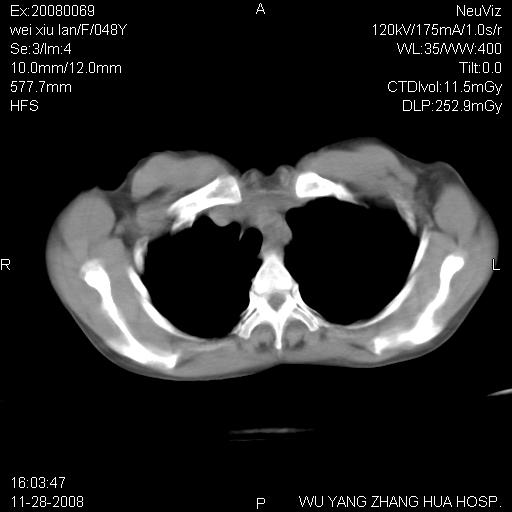

标题: CT16847:女,48岁,咳嗽,发热两日,平常偶有上腹部不适。 [打印本页]

标题: CT16847:女,48岁,咳嗽,发热两日,平常偶有上腹部不适。

这个是左侧膈膨升伴不完全性胃翻转,手术将松弛的左横膈膜折叠缝合即解决问题。

考虑 膈疝或食管裂孔疝或膈膨升,建议透视下吞钡观察明确

膈疝或食管裂孔疝或膈膨升,建议透视下吞钡观察以进一步明确。

左膈顶及肋膈角均上移,膈面光滑,考虑左膈肌麻痹